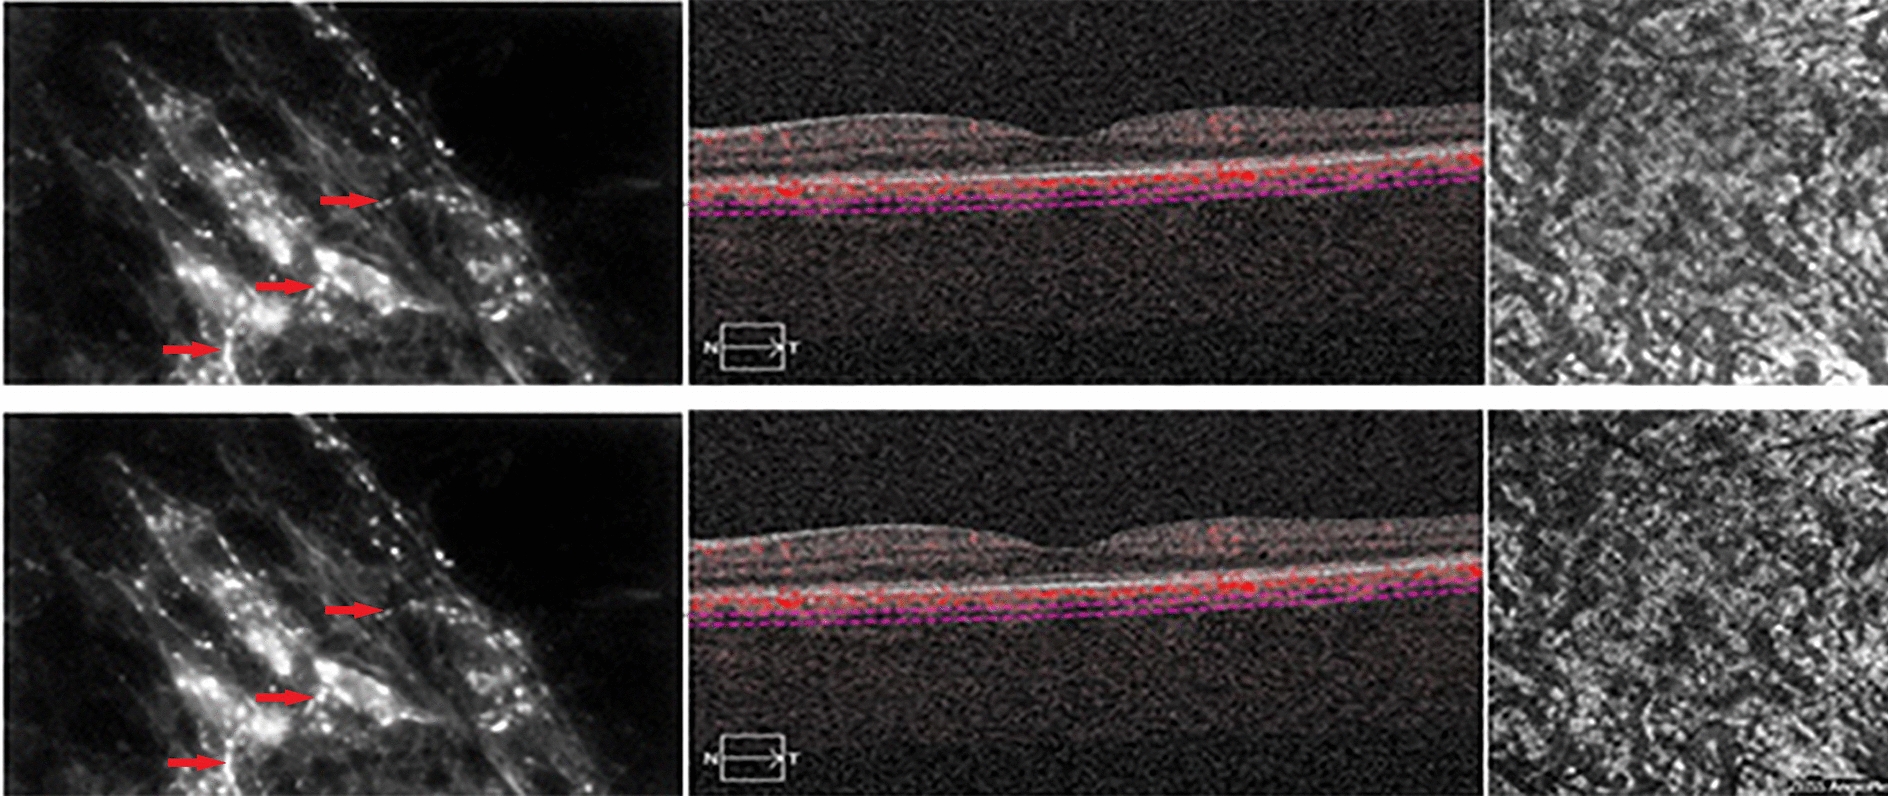

The perivascular and intravascular adrenergic innervation (hyperfluorescent in histological images), which contracts relationship with the melanocytes at the level of the choroidal vascular lamina, have not been identified in the OCT-B scan images, in which the stroma of the different layers appears uniformly hyper-reflective. The vascularization in the different layers is visualized as intensely black areas well delimited both in the OCT-B images and in the “en face” images, especially for large and medium-sized vessels. The “en face” images did not provide information on the distribution of intrastromal and perivascular nerve fibers and melanocytes, as part of the background hyperreflectivity of the choroidal stroma (Fig. 8).

Fig. 8.

Intervascular adrenergic nerve fibers (red arrow) in contact with melanocytes (blue arrow, images from the left) and visualization of choriocapillary layer in B-Scan OCT + OCT-A (images in the middle) and “en face” OCT (upper-right image) and OCT-A (lower-right image). The Sattler layer is not clearly visible in OCT-A due to the reflective properties of retinal pigment epithelium

Histological findings and OCT- angiography images compared

In OCT-A images, the choriocapillary layer appears to be granular, with hyper-reflective areas alternating with hyporeflective zones, without an evident delimitation of the capillaries. In some choriocapillary angiographic images, it is possible to visualize some artifacts due to the projection of the retinal vessels on the underlying choroid. Similarly to “en face” images, the stroma of the vascular lamina appears uniformly hyper-reflective, alternated with well-defined and branched hyporeflecting areas, which characterize the medium and large caliber blood vessels. The adrenergic fibers or other neural properties at the stroma level of the Sattler and Haller layers cannot be identified (Fig. 9).

Fig. 9.

Adrenergic nerve fibers in intervascular spaces (red arrow, images from the left) and visualization of Haller layer in B-Scan OCT + OCT-A (images in the middle) and “en face” OCT (upper-right image) and OCT-A (lower-right image)